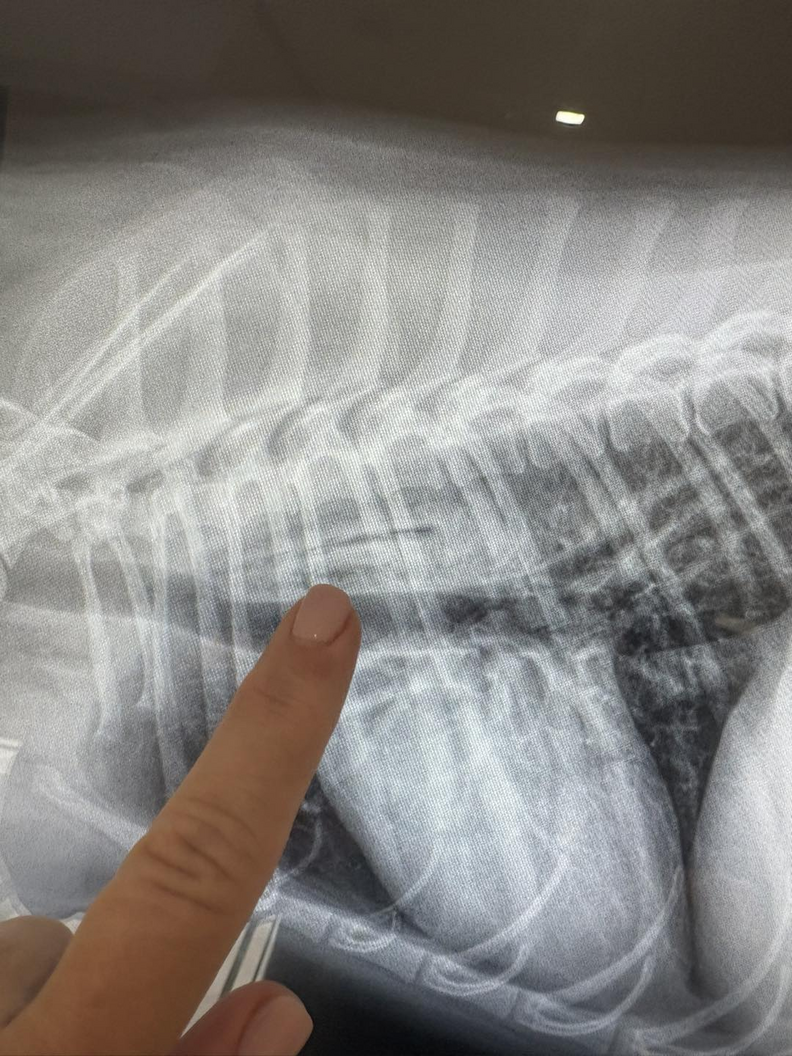

No mango seed was found in Luna’s stomach, and even worse, Luna was sicker than ever. That’s when they did a barium study and sent the X-rays to a specialist, and the results this time were shocking.

“You could barely, barely see it,” McKnight said. The “it” was the mango seed — lodged horizontally in Luna’s throat.

“That’s when the pieces started falling together, and it was just like a race against the clock,” McKnight explained. “We now know when she went to swallow, it was just like a totally ripping, piercing pain.”